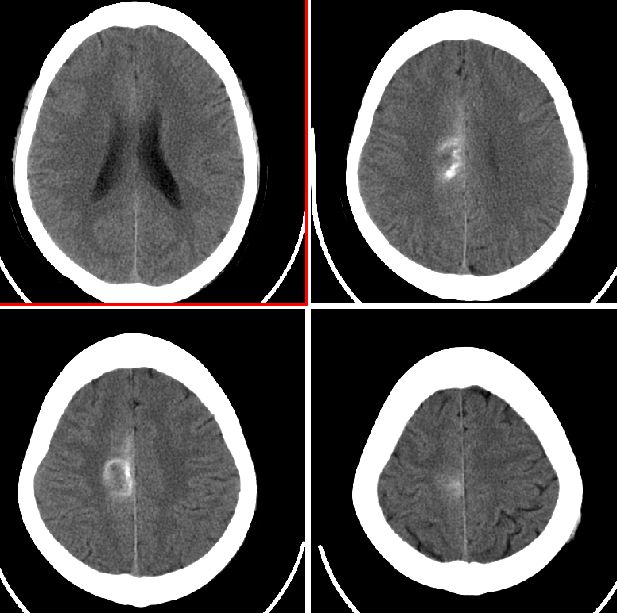

ct

ct表现:右侧中央旁小叶区团状混杂密度病灶,周边不完整环状钙化,病灶周围脑组织无水肿。